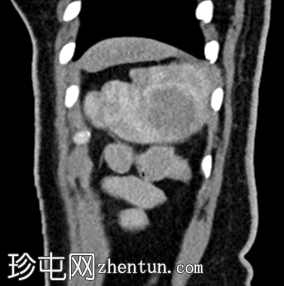

矢状位增强扫描

动脉期

脾脏内可见一圆形低密度病灶,动脉期呈周边环状强化,延迟期呈轻微向心性充盈

学特征为:病灶周围呈放射状强化,中心呈放射状强化,周围环状强化,中心充盈轻微。增强扫描后可见中央星状瘢痕。